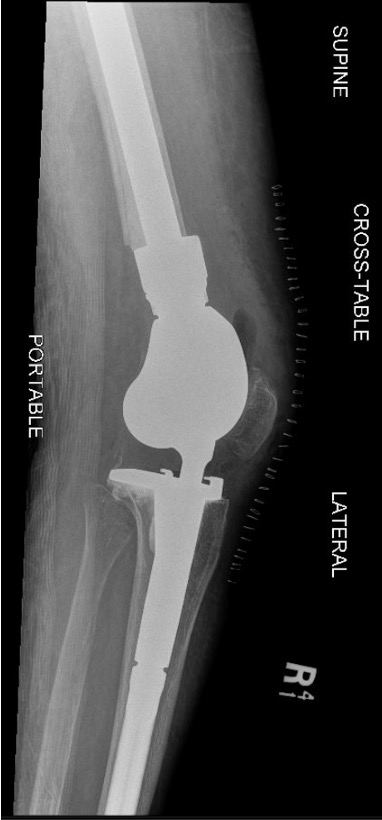

5. Distal femoral replacement

Distal Femoral Replacement

Indications

Elderly osteoporotic patient

Unreconstructable distal femur

Multiple co-morbidities

Difficulty non weight bearing

Results

Hart et al. J Arthroplasty 2017

- ORIF v distal femoral replacement in patients > 70 years old

- reoperation rate 10% in both groups

- 20% non union in ORIF

- at one year, 1/4 ORIF patients wheelchair bound, all DFR patients ambulatory

- AOANJRR review of DFR in native knees

- 10% revision rate at 3y

- most commonly loosening > infection